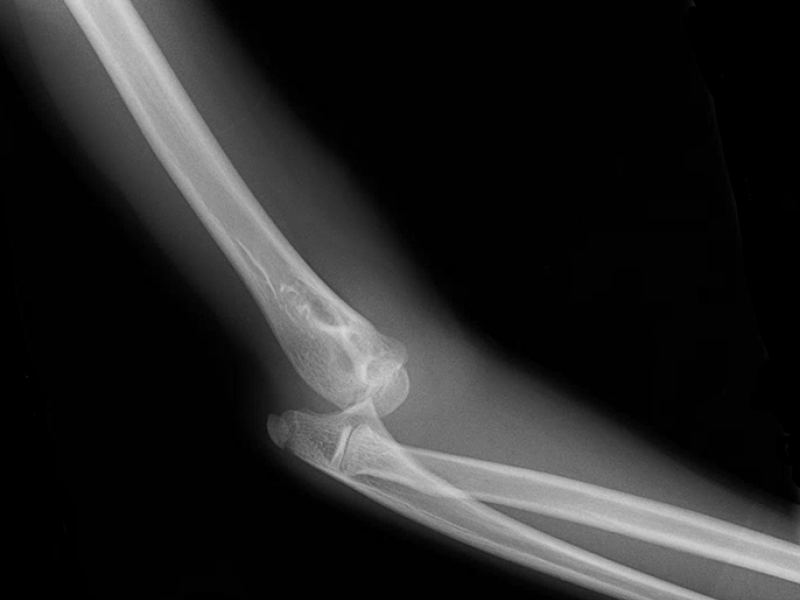

A 13 yo F presents to the ED with R elbow pain after falling